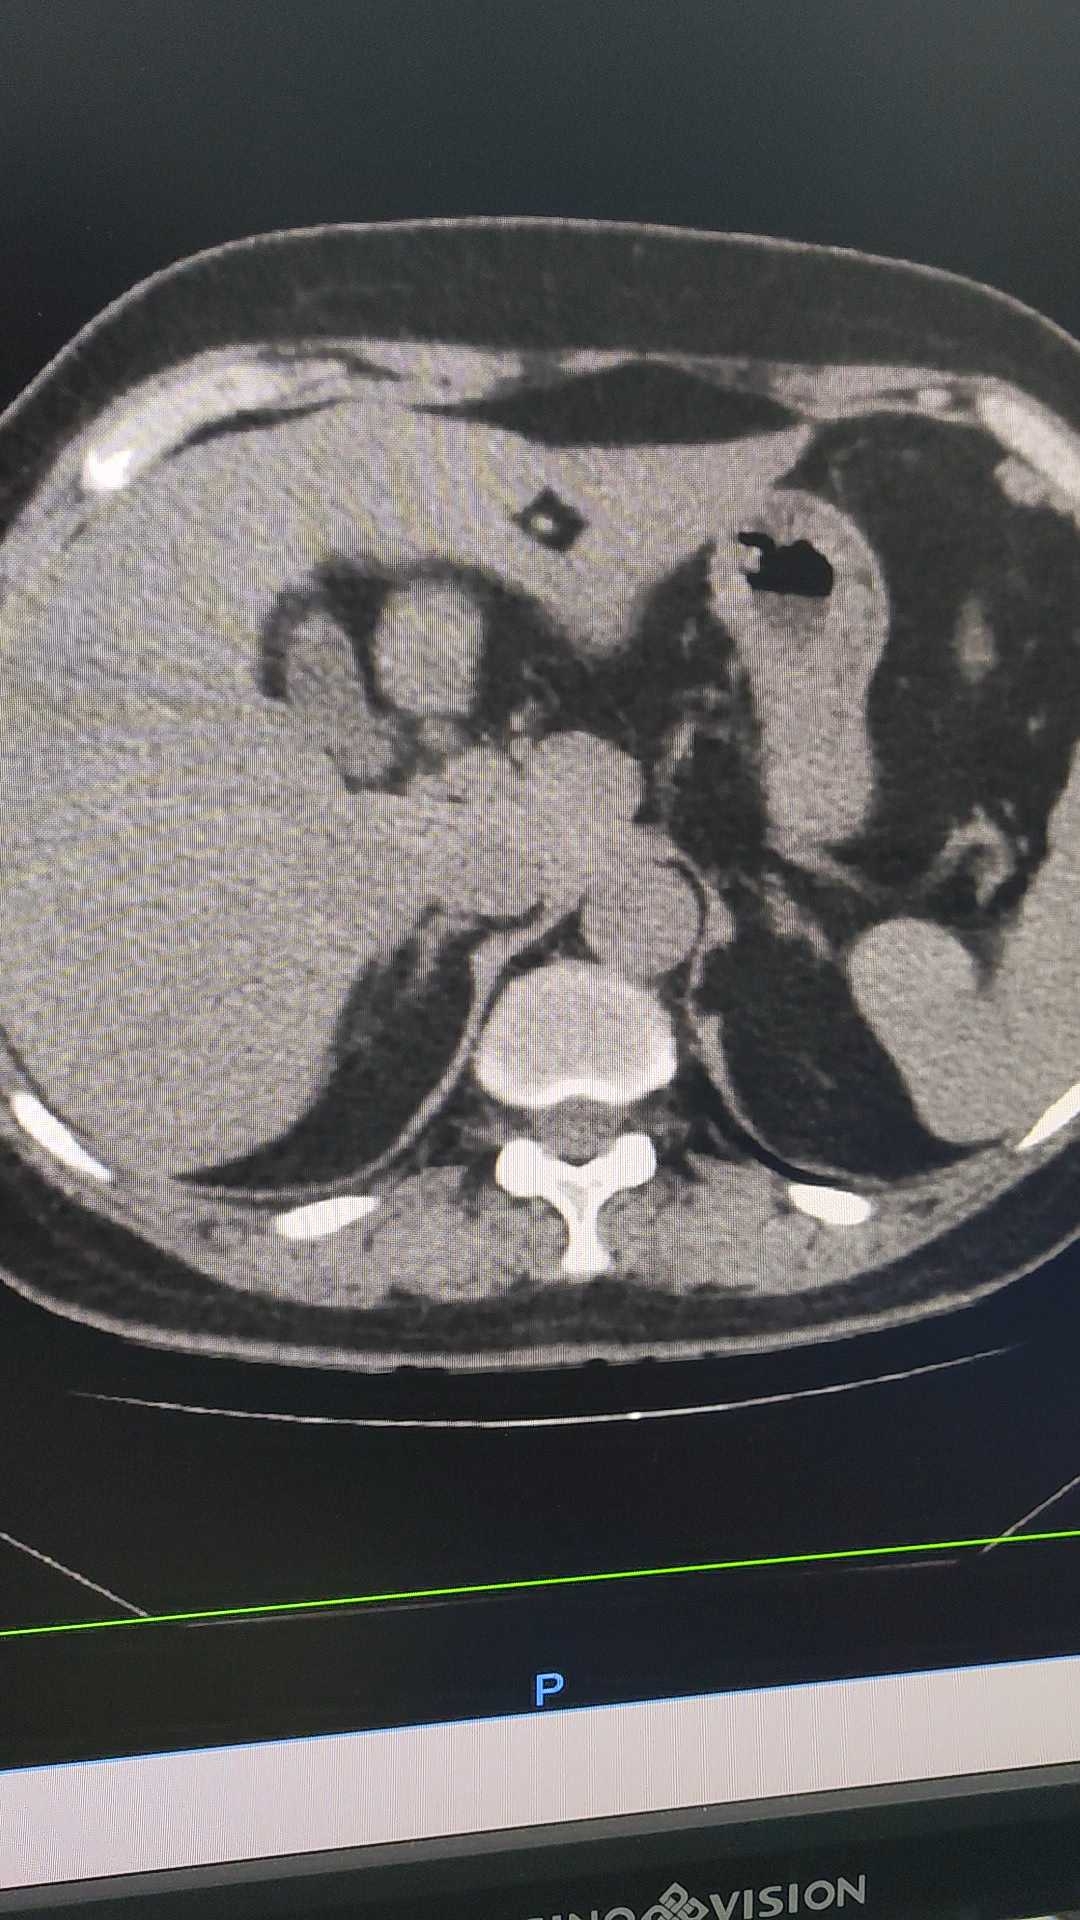

【病例】胆囊腺肌症1例ct影像表现

【病例】胆囊腺肌症1例ct影像表现 – 影像ppt